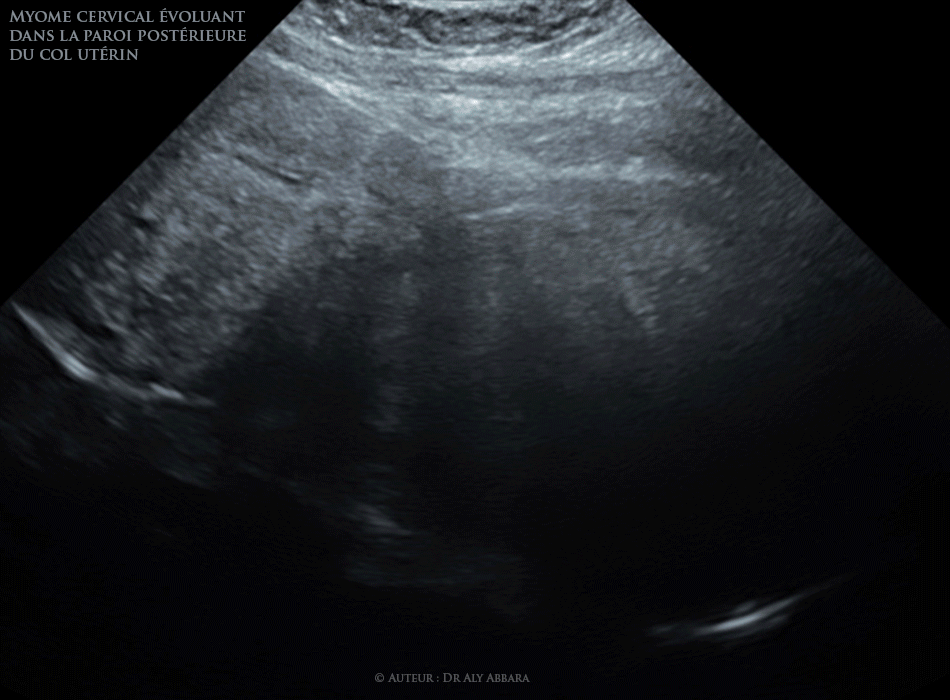

• Il s'agit d'un myome cervical évoluant dans la paroi postérieure du col utérin et occupant la cavité vaginale.

Ce volumineux myome (10.80 x 10,97 x 9.65 cm soit 535 g) a été mis en évidence chez une patiente âgée de 48 ans consultant pour métrorragie avec une anémie (hémoglobine à 7,6 g/dl), et surtout une rétention urinaire complète par compression de l'urètre et le col de la vessie.

Les données chirurgicales confirment la localisation et le poids (myomectomie totale par morcellement par voie vaginale).